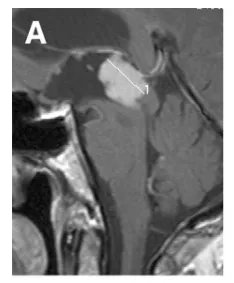

49岁男性患者,临床表现为头痛、恶心及呕吐。影像学检查发现第三脑室后部巨大强化病灶(A)。对于因中脑导水管受压导致梗阻性脑积水的肿瘤,最根本的脑脊液循环恢复策略仍是肿瘤全切除。然而多数瘤体过大,难以单纯经内镜彻底切除。

采用先行神经内镜第三脑室造瘘(B-F内镜下视野),再行开颅肿瘤切除的方案,具体过程如下:

(B)室间孔(Monro孔),选择可同时抵达第三脑室底及肿瘤的手术入路